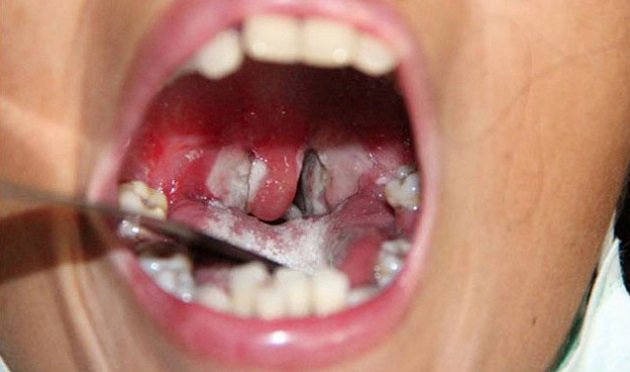

+ Khám thấy có giả mạc. Cần phân biệt tính chất của giả mạc bạch hầu với giả mạc mủ. Giả mạc bạch hầu thường trắng ngà hoặc mầu xám dính chặt vào xung quanh tổ chức viêm, nếu bóc ra sẽ bị chảy máu. Cho giả mạc vào cốc nước dù có khuấy mạnh cũng không tan. Còn giả mạc mủ thì sẽ bị hoà tan hoàn toàn trong cốc nước. Vùng niêm mạc xung quanh giả mạc bị xung huyết.